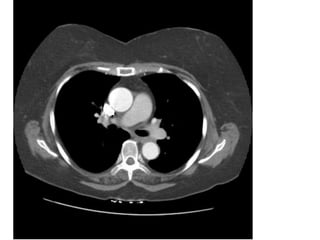

Figure 18. Tăng áp động mạch phổi thứ phát sau PE mạn ở bn nam 62 tuổi

(cùng của bn hình 12).

- Đường kính động mạch phổi 41 mm. (bình thường < 30 mm).